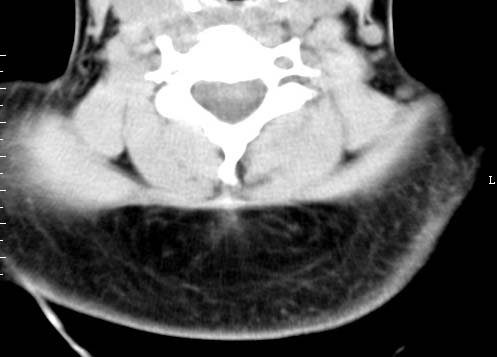

以下是引用sos.la在2008-6-24 5:29:00的发言:[br]可疑项部皮下脂肪肉瘤.穿刺活检.

以下是引用pujunzhi在2008-6-24 7:29:00的发言:[br]后颈部脂肪瘤

以下是引用随光逐影在2008-6-24 7:46:00的发言:[br]考虑项部皮下脂肪瘤或脂肪沉积。